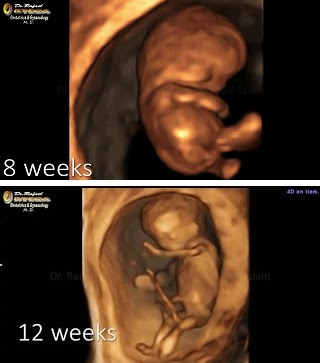

Pues parece que eso no va con esta gente que gobierna España. Leo mucho sobre libertad sexual y demás, pero hace muchísimo tiempo que no leo nada sobre métodos anticonceptivos. Es decir, que se están promocionando unas actividades que llevan de cabeza a una inmensidad de embarazos no deseados. Y cuando llega ese embarazo no deseado parece que lo que los gobernantes quieren es que se produzca el aborto. Ni tan siquiera desean que la mujer embarazada tenga la opción de saber lo que lleva en su vientre, a través de la tecnología existente.

Pareciera que lo que desean es que cuanto más abortos, mejor. Pasando por encima de la vida del no nacido, pero también de la libertad de la mujer embarazada para tomar la decisión, la que sea, con toda la información en su mano.